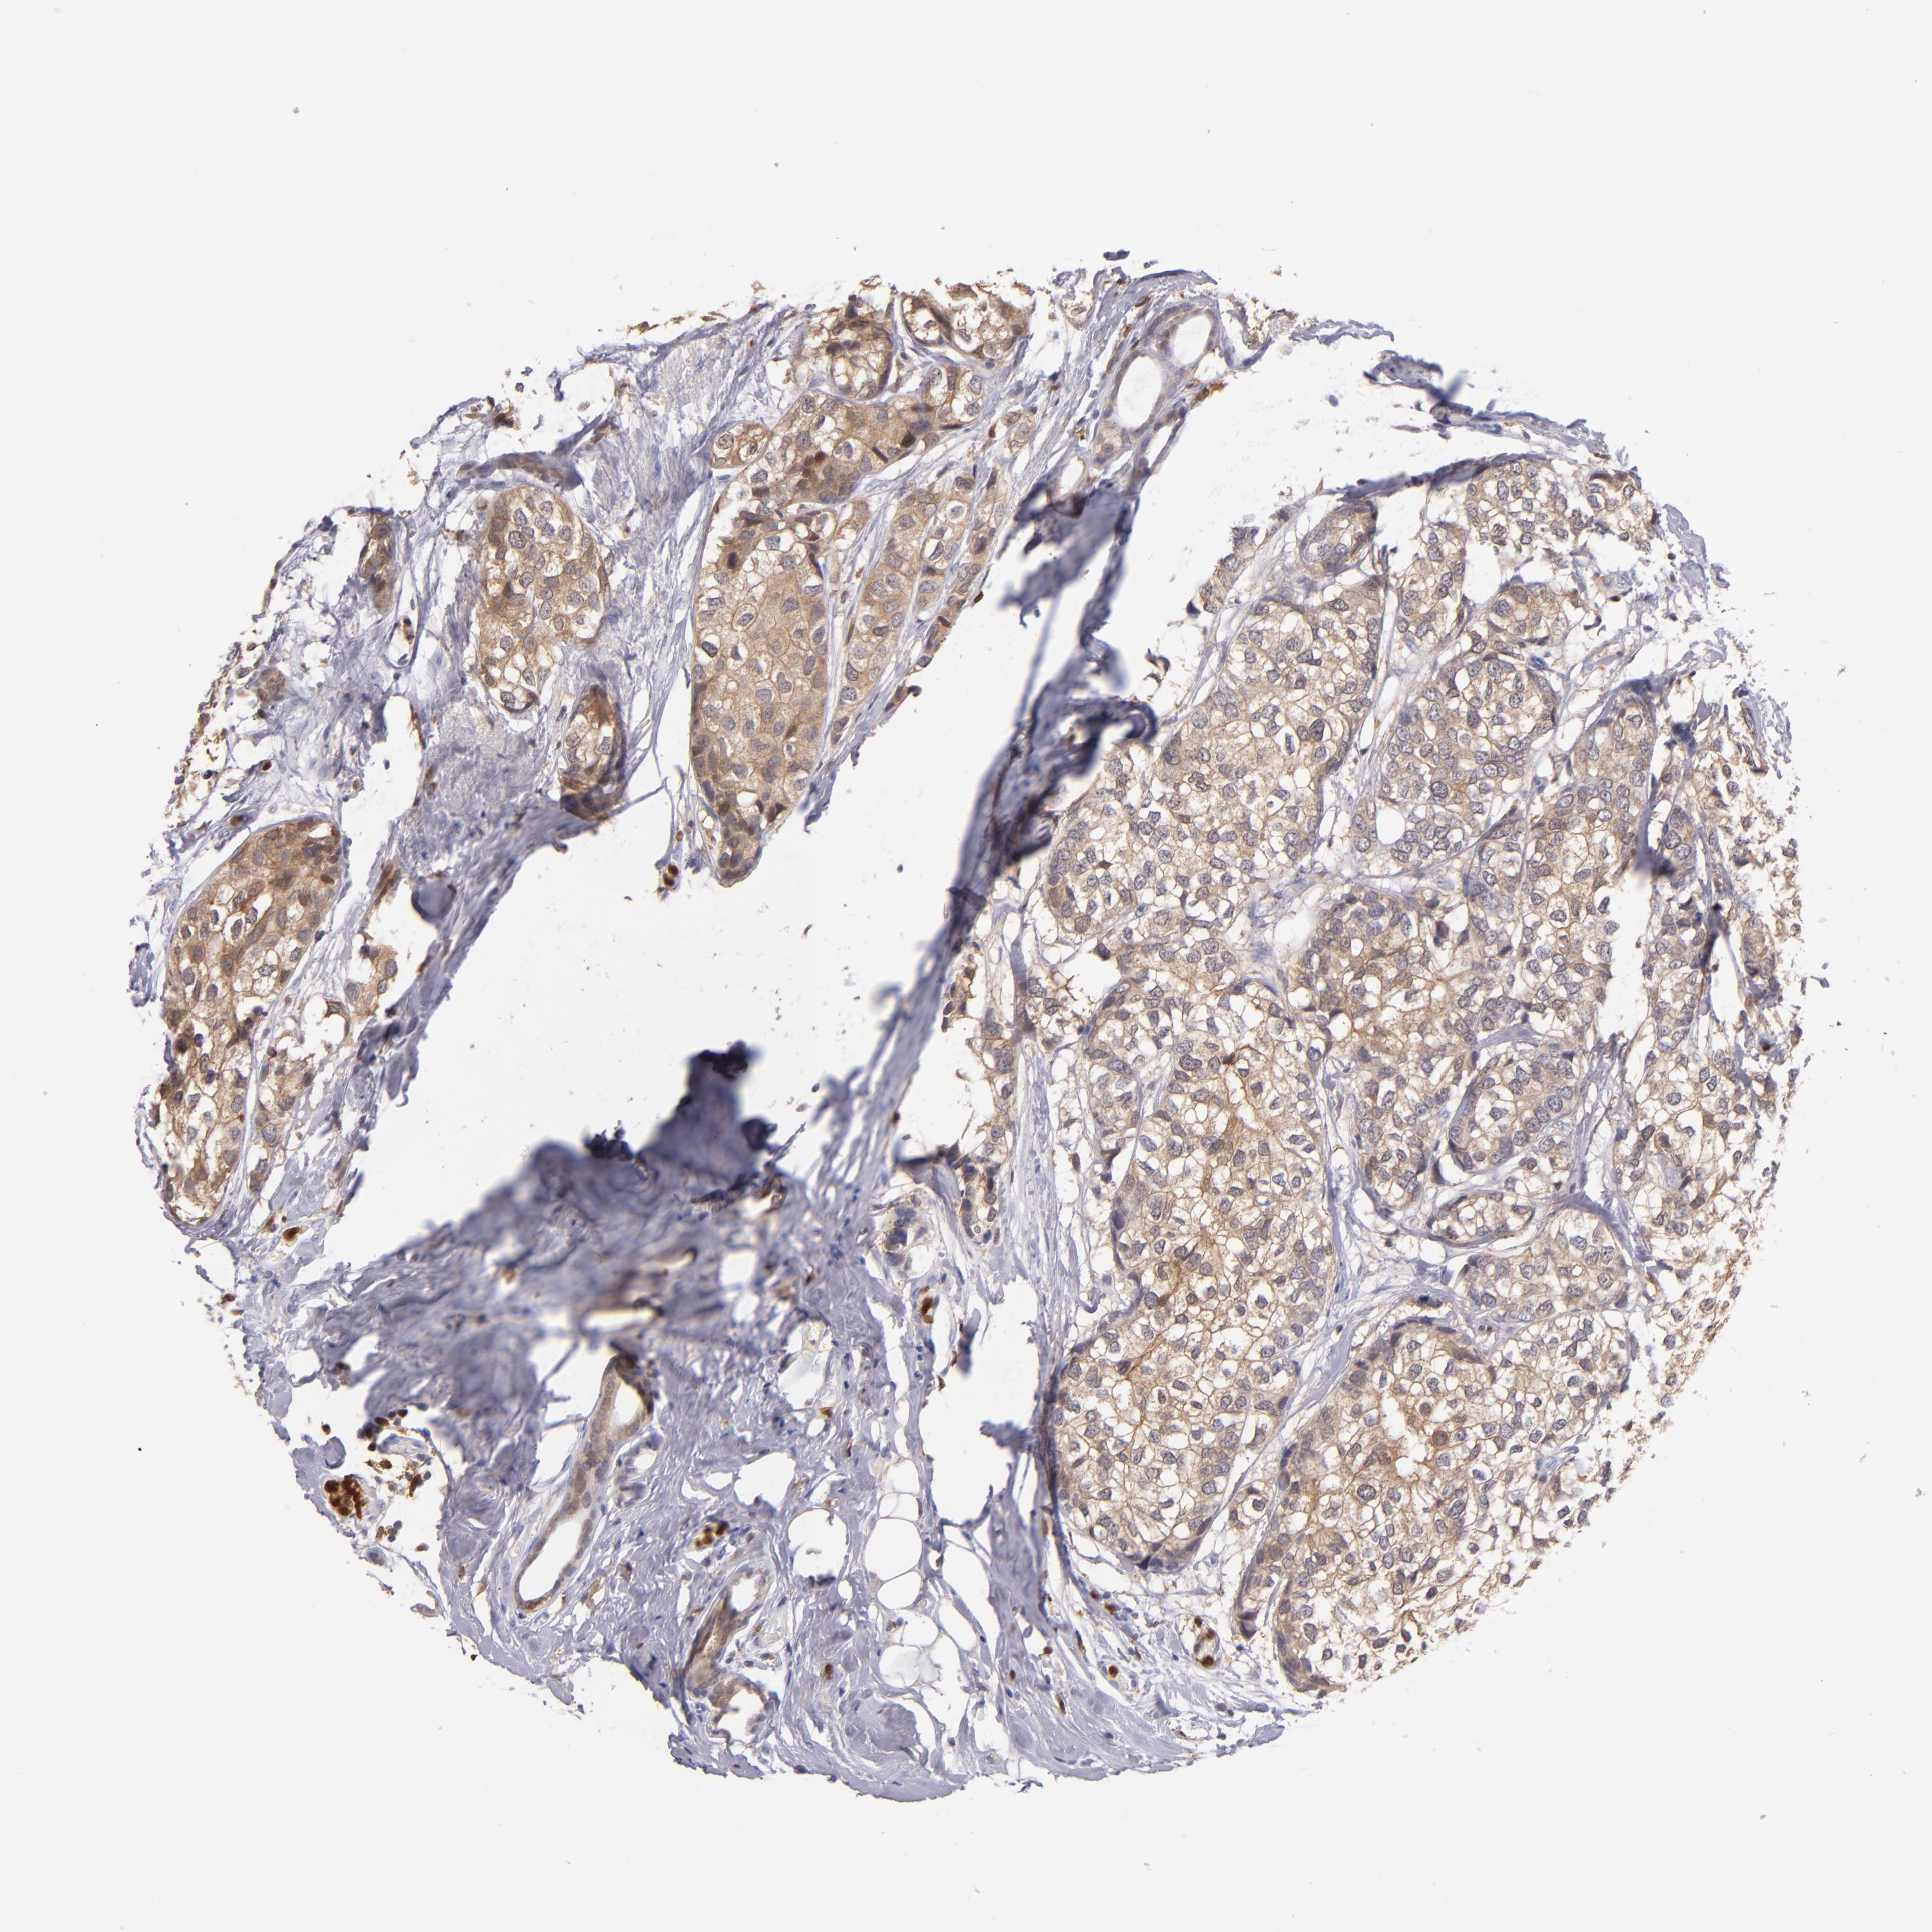

CANCER BREAST CANCER Show tissue menu

BRCA TCGA BRCA VALIDATION PROTEIN EXPRESSION